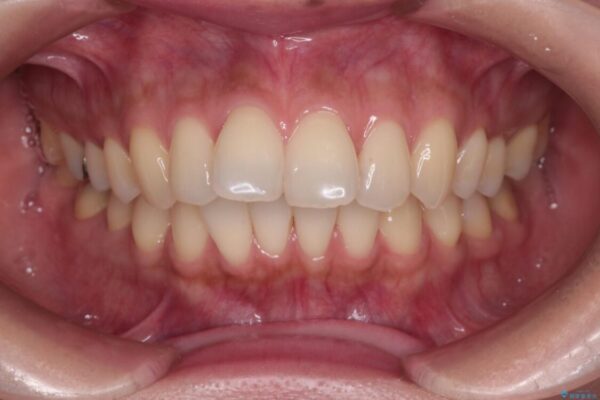

治療後について

インビザラインにて抜歯矯正を行うと、高頻度で奥歯が咬み合わなくなります。

また、抜歯スペースに向けて奥歯が移動する際、必ず傾斜して移動するため、仕上がりの咬み合わせはワイヤー矯正と比べて明らかに劣ります。

抜歯スペースが閉じてからも咬みにくさ改善のためマウスピース矯正を継続するため、治療期間は長期化します。

治療後

• 上顎前歯の突出を軽減 インビザラインによる抜歯矯正 治療後画像